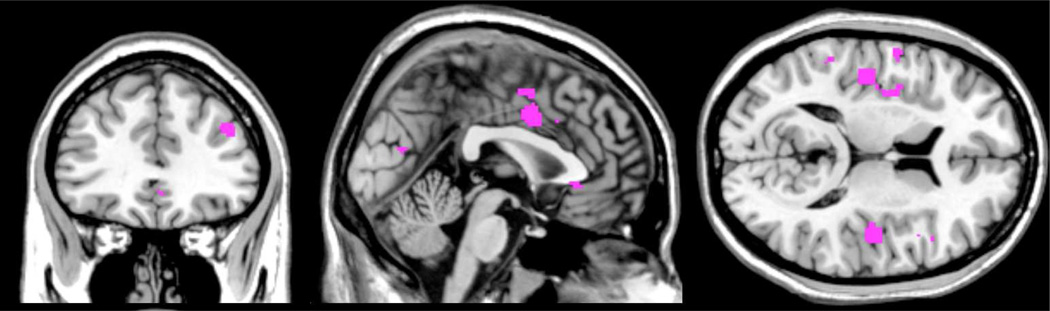

As illustrated in Figure 1, there is substantial overlap in the brain regions that have been linked to both CRPS and to systemic inflammation independently: notably the middle cingulate, posterior insula, dorsolateral prefrontal cortex and the parietal lobule. Moreover, there may be overlap between inflammatory responses and the structural changes observed in CRPS (Baliki et al. 2011; Geha et al. 2008), i.e. the ventral medial prefrontal cortex and the anterior insula and the nucleus accumbmens.

Fig. 1.

Shared activation in CRPS processing and cytokine related activation, illustrating the potentially shared networks between the conditions. The Activation Likelihood Estimate (ALE) overlap was created as the conjunction of ALE maps from CRPS and cytokine related fMRI studies, not corrected for multiple comparisons.